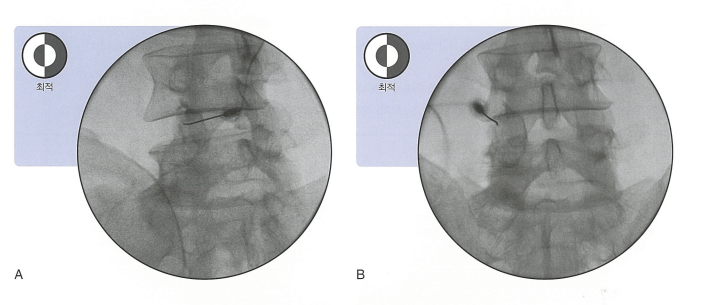

아래와 같이 바늘을 위치시키고 약을 드리게 됩니다. 치료 목적 외에도 진단 목적으로 사용하기도 합니다. 실제로 허리가 아픈 원인이 관절떄문인지 확실히 알고 싶을 떄, 주사로 좋아지는지를 통해서 거꾸로 알 수 있기 떄문입니다.

아래 그림 처럼 바늘(그림에서는 녹색으로 표시)을 위치시키고, 약을 드리게 됩니다. 비교적 주사 시에 발생하는 통증이 적고, 시술 시간이 상대적으로 짧은 것이 장점입니다. 그래서 최근에 정말 많이 사용되는 주사(시술)입니다.

아래 그림에서처럼 바늘을 위치시키고 약을 주게 됩니다

x-ray상에서는 다음과 같은 조영제 음영으로 공간을 확인하고, 약을 드립니다